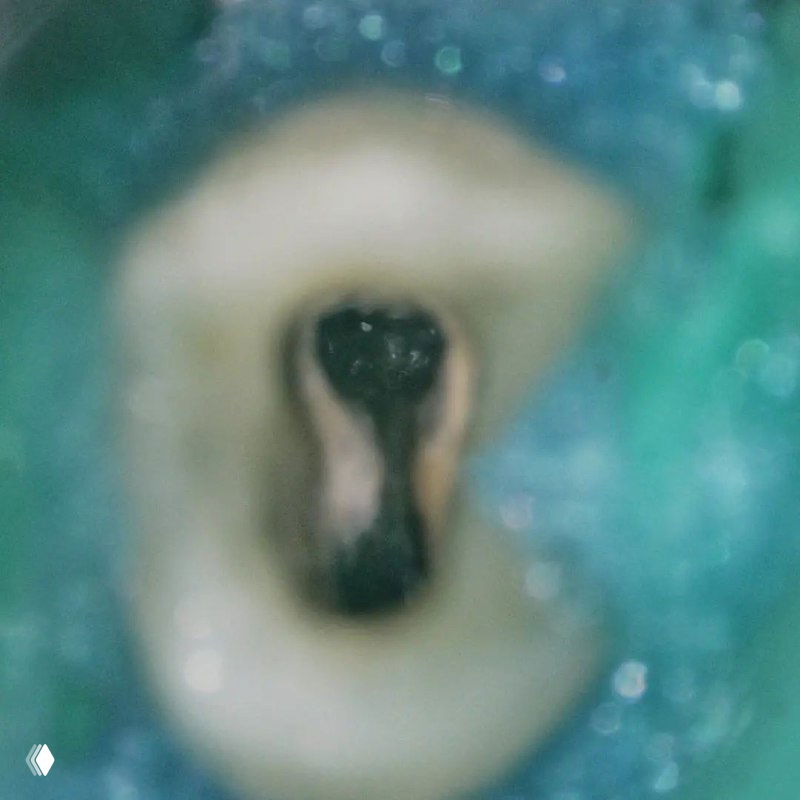

- классическую овальную полость доступа нужно немного расширить в области щёчных каналов в мезио-дистальном направлении

- проводить аккуратное расширение щёчных каналов, так как в области данных корней очень мало дентина (в моём случае расширение 25.04)